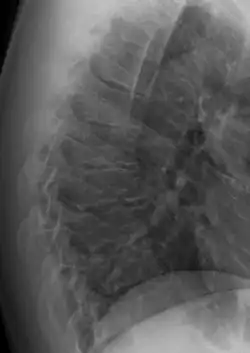

Scheuermann's disease is a skeletal disorder.[3] It describes a condition where the vertebrae grow unevenly with respect to the sagittal plane; that is, the posterior angle is often greater than the anterior. This uneven growth results in the signature "wedging" shape of the vertebrae, causing kyphosis. It is named after Danish surgeon Holger Scheuermann.[4][5][6]

Scheuermann's disease is considered to be a form of osteochondrosis of the spine. It typically develops during adolescence and presents a significantly worse deformity than postural kyphosis. Patients with Scheuermann’s kyphosis cannot consciously correct their posture. The apex of their curve, located in the thoracic vertebrae, is quite rigid.

In addition to the pain associated with Scheuermann's disease, many individuals with the disorder have loss of vertebral height, and depending on where the apex of the curve is, may have a visual 'hunchback' or 'roundback'. It has been reported that curves in the lower thoracic region cause more pain, whereas curves in the upper region present a more visual deformity. Nevertheless, it is typically pain or cosmetic reasons that prompt sufferers to seek help for their condition. In studies, kyphosis is better characterized for the thoracic spine than for the lumbar spine.[7][8]

The seventh and tenth thoracic vertebrae are most commonly affected. It causes backache and spinal curvature. In very serious cases it may cause internal problems and spinal cord damage. The curvature of the back decreases height, thus putting pressure on internal organs, wearing them out more quickly than the natural aging process; surgical procedures are almost always recommended in this case.

Diagnosis is typically by medical imaging. The degree of kyphosis can be measured by Cobb's angle and sagittal balance.